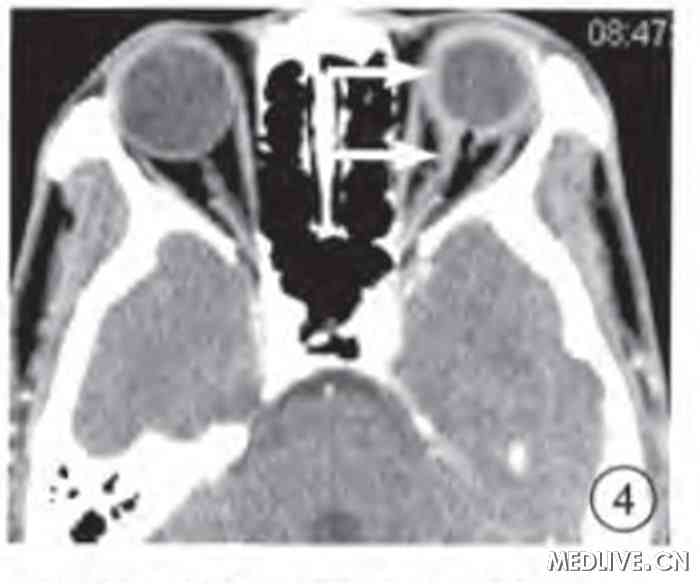

图4 玻璃体腔气体抽出手术后左眼CT横断面软组织窗像。玻璃体腔、视神经鞘内积气消失,视神经显示,视神经、眼球壁轻度增厚(白箭)。

图5 玻璃体腔气体抽出手术后CT横断面软组织窗像。蛛网膜下腔内仍有少量积气(白箭)。